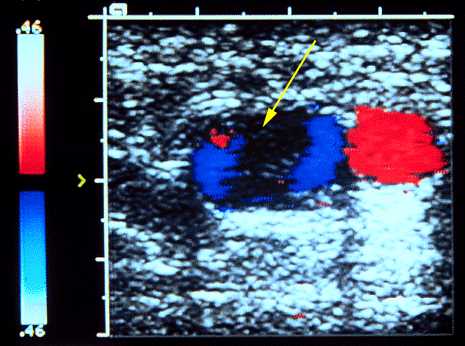

Figure 6: Color-Flow-Doppler-ultrasound

Color-flow-Doppler-ultrasound is a highly sensitive and specific test for deep-vein thrombosis. It combines the ability to detect changes in venous flow and venous collapse under the ultrasound probe pressure using color Doppler visual display. This image shows a non-compressible filling defect in the vein, consistent with deep-vein thrombosis (arrow).